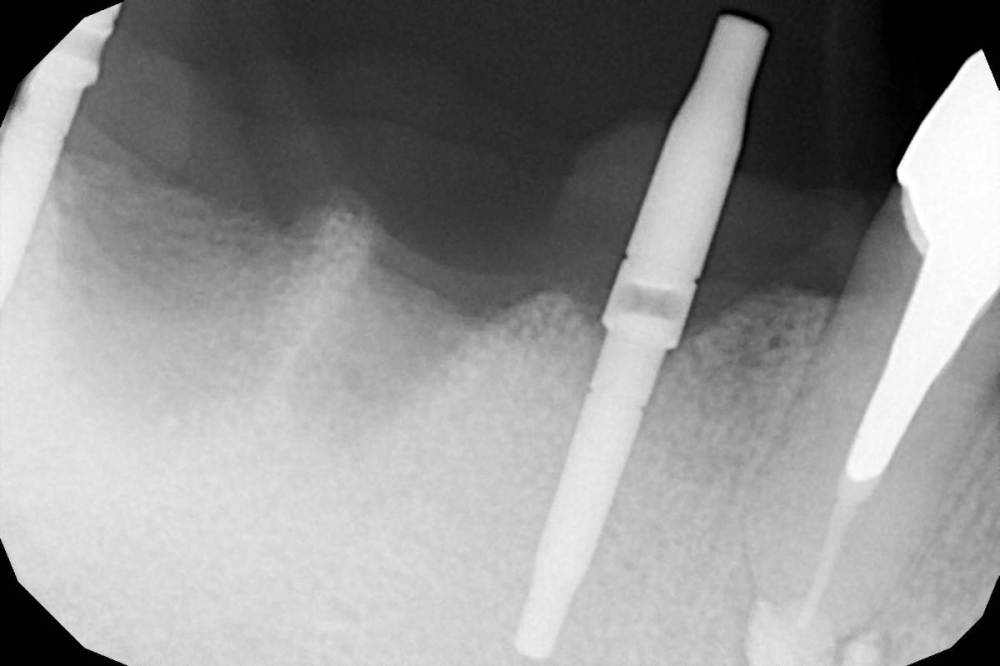

Коллеги, во время пилотного сверления как в области 4.5 так и в области 4.7 пациент отметил резкую боль. Если покрутить КТ, то как раз в местах планируемых имплантатов есть небольшие костные дефекты (хотя конечно на дефект это не тянет, тогда как называть?).

"Углубление" у 4.7